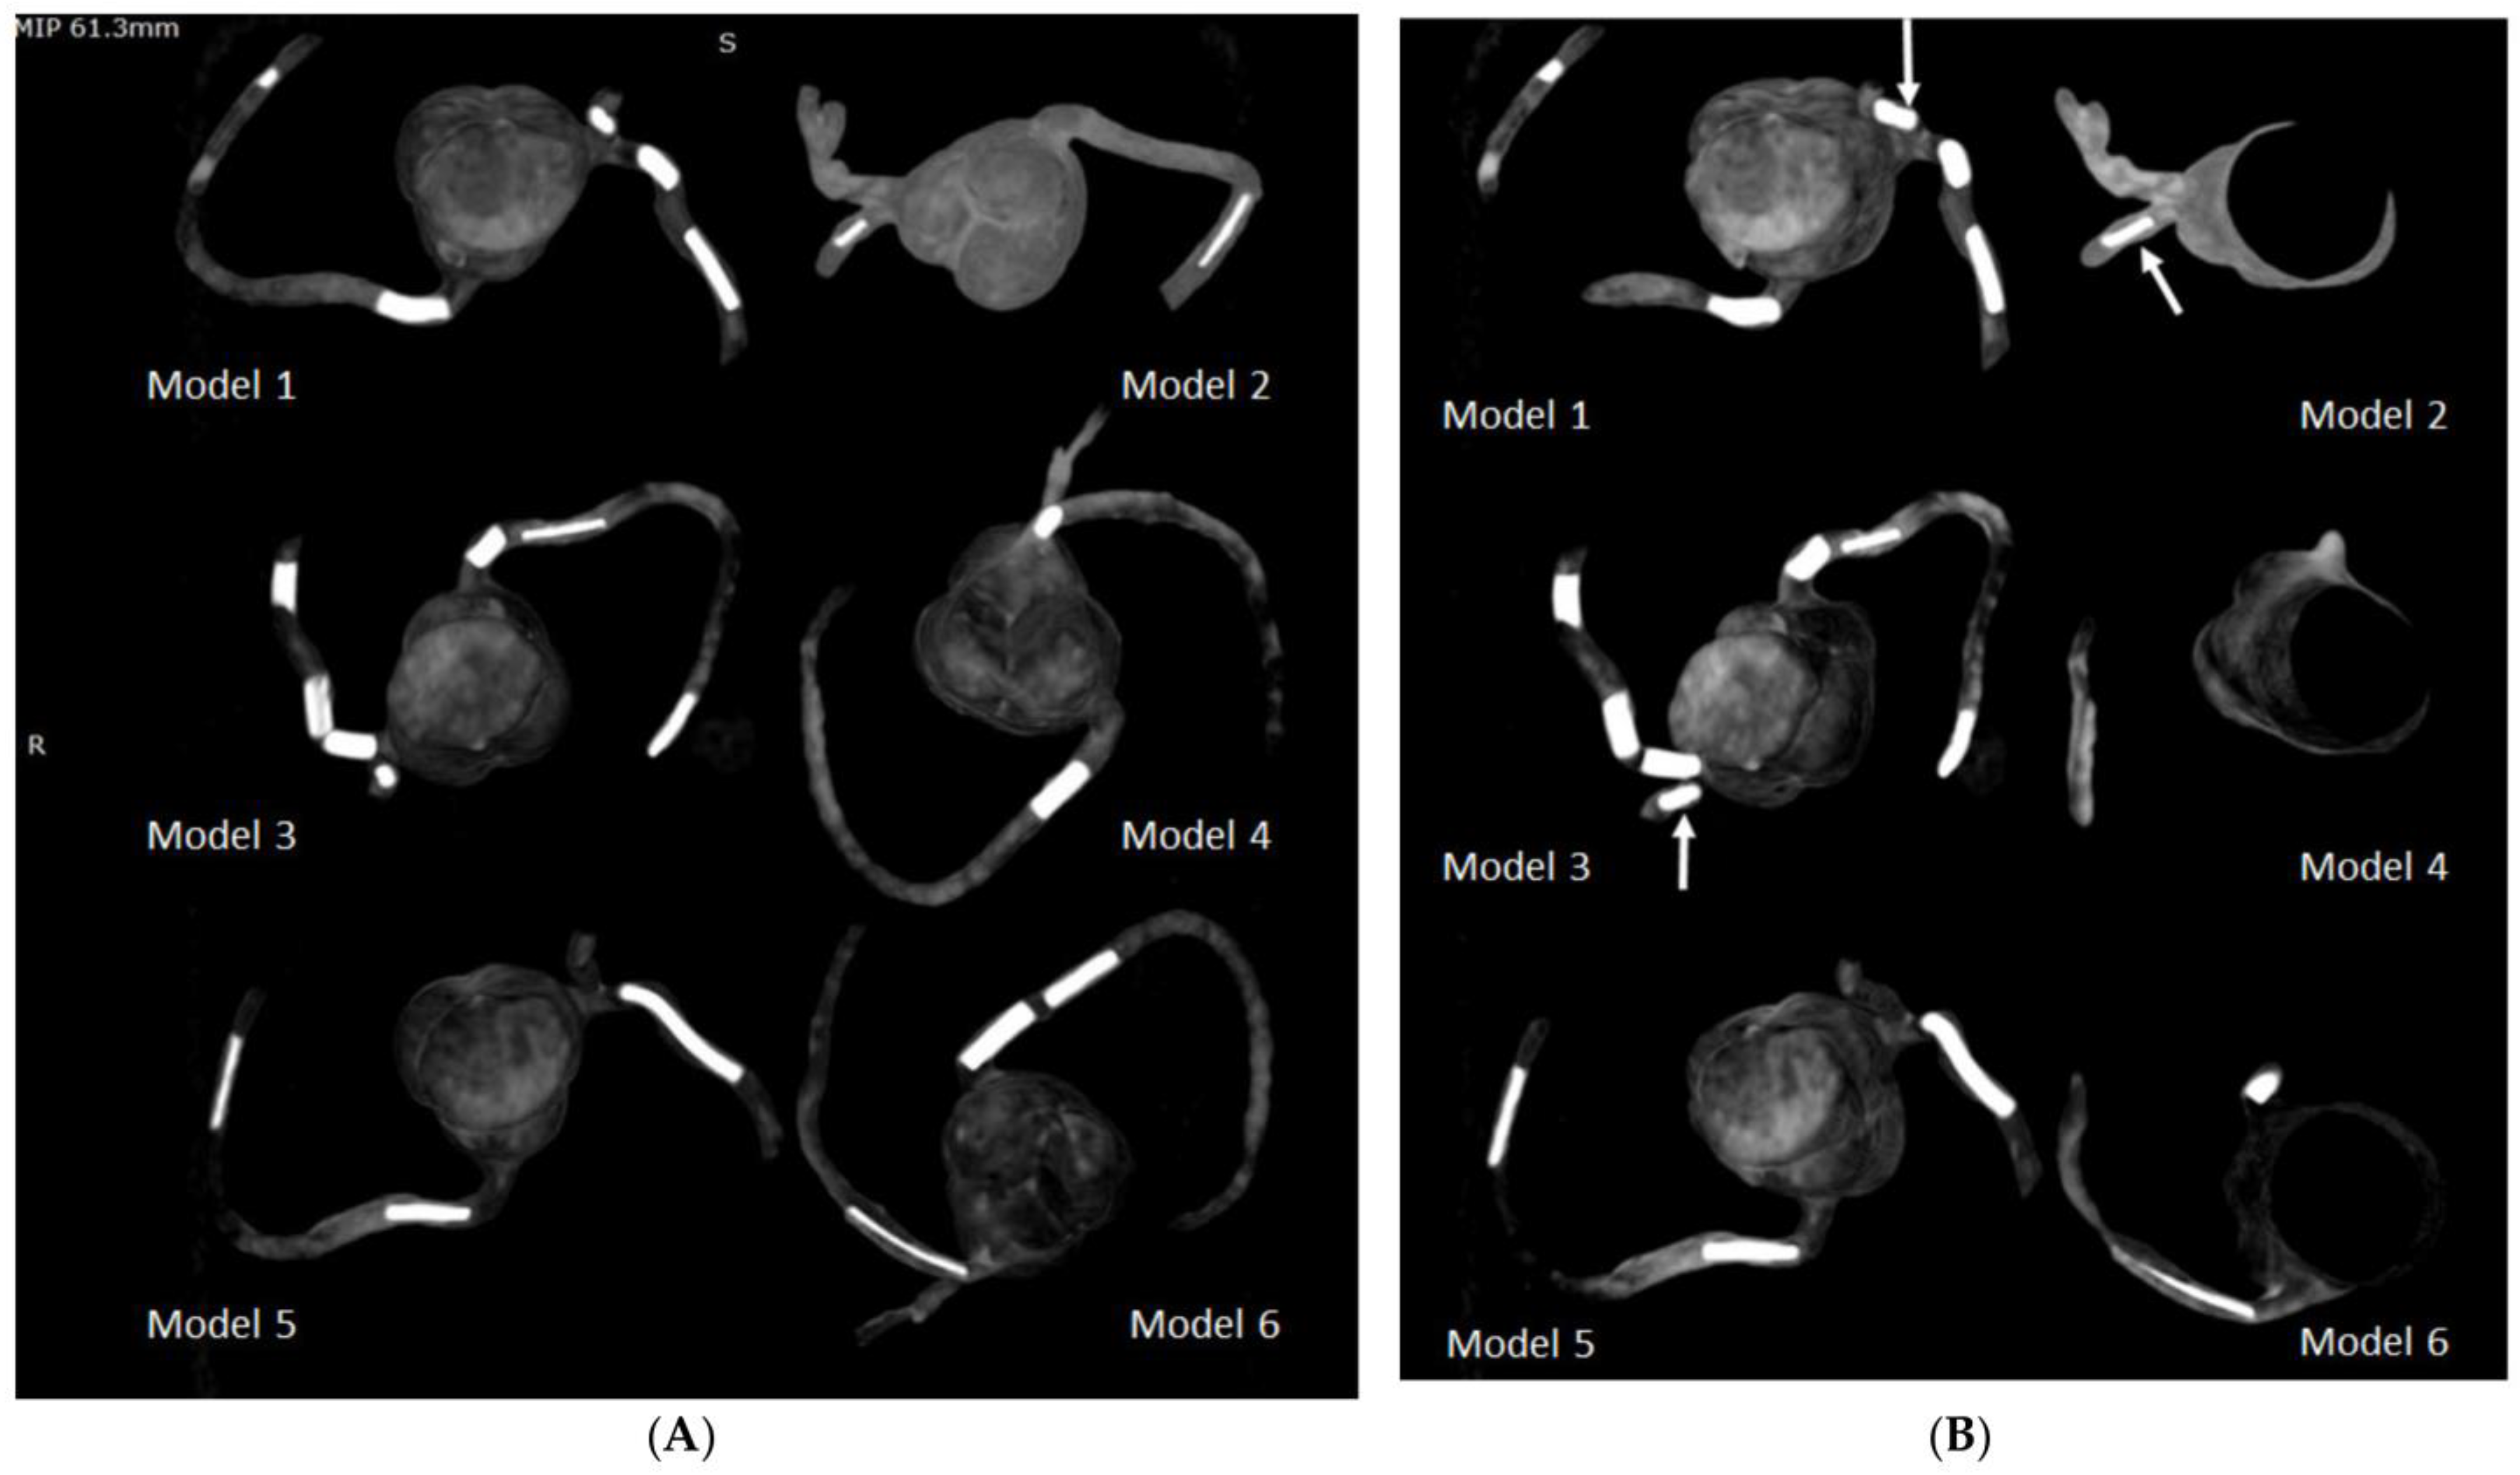

4.1. 3D-Printed CHD Model Accuracy

- Lee, S.; Squelch, A.; Sun, Z. Quantitative assessment of 3D printed model accuracy in delineating congenital heart disease. Biomolecules 2021, 11, 270. [Google Scholar] [CrossRef] [PubMed]

- Lau, I.; Wong, Y.H.; Yeong, C.H.; Abdul Aziz, Y.F.; Md Sari, N.S.; Hasim, S.A.; Sun, Z. Quantitative and qualitative comparison of low- and high-cost 3D-printed heart models. Quant. Imaging Med. Surg. 2019, 9, 107–114. [Google Scholar] [CrossRef] [Green Version]